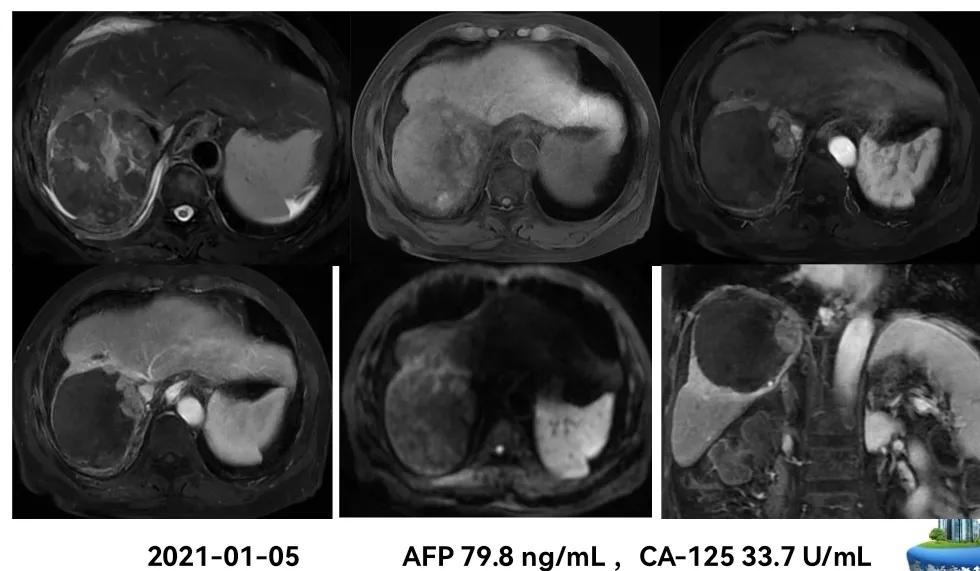

影像学检查:

治疗过程中肿瘤标记物甲胎蛋白(AFP)的变化